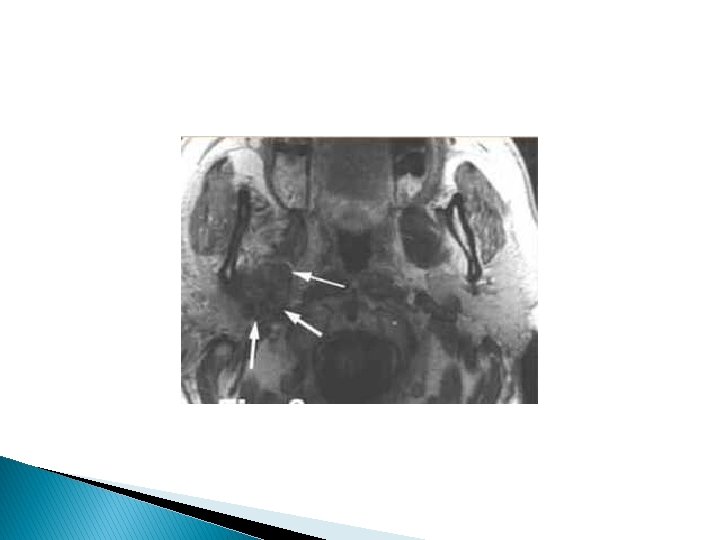

Méningo-radiculite métastatique